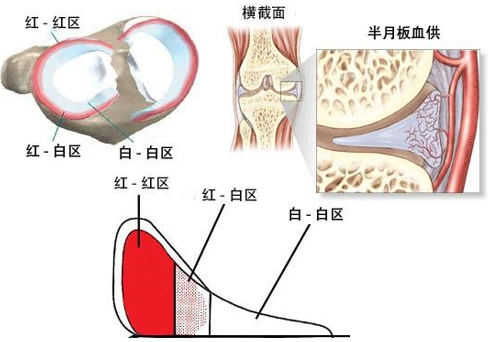

红白区示意图

Muller 等将半月板分为三个区,即红-红区、红-白区及白-白区。红表示有血运,白表示无血运。红-红区撕裂位于滑膜缘有血运区,即撕裂之两侧缘均有充足血供,愈合能力很强。红-白区撕裂位于有血运和无血运的分界部,也有一定的愈合能力。而白-白区则完全无血运极难愈合。红-红区及红-白区撕裂在妥善的修复后均可愈合。